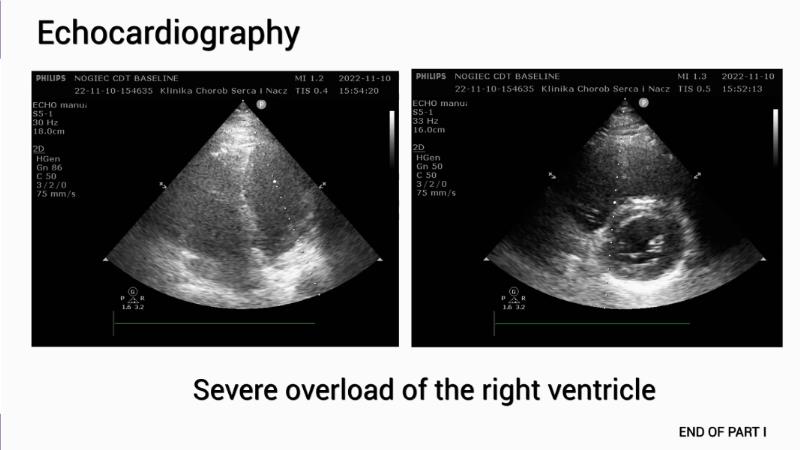

Advancing percutaneous treatment of pulmonary embolism with computer-assisted vacuum thrombectomy

Join this session to delve into innovations in computer-assisted vacuum thrombectomy for acute pulmonary embolism, leveraging real-life case scenarios to share practical experiences and discuss treatment strategies. Amidst the current surge in scientific research, ongoing trials like STORM PE and STRIKE PE are pivotal in shaping the landscape of pulmonary embolism management.